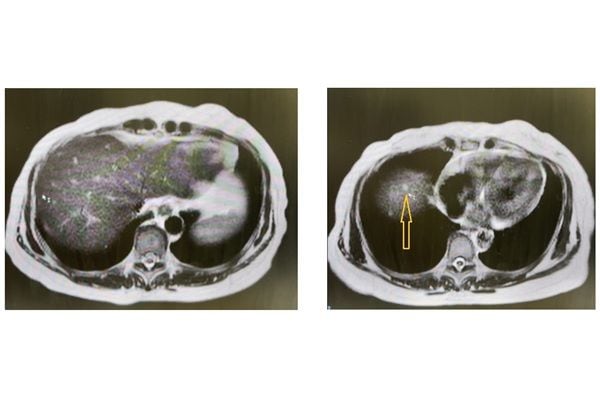

まずMRIの画像で肝臓を見ると、肝嚢胞という水の塊がありますが、これは問題ありません。全体をくまなく見ても、悪いものはありませんね。周辺の臓器がはっきり見えるのも特長で、肝臓の右側(右葉)下方にある胆のうも正常です。

筆者の肝臓。右図の白く光っているのが肝嚢胞